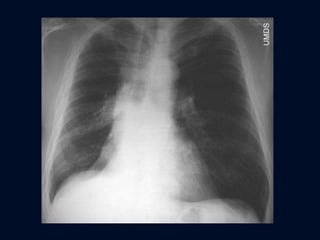

ATELECTASIA PULMONAR TOTAL Opacidad  del hemitórax Elevación del hemidiafragma  Desviación completa del mediastino Sobreinsuflación que pasa la línea media

ATELECTASIA PULMONAR TOTAL